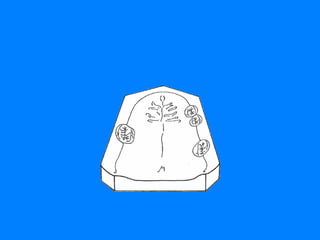

CLASE I DE KENNEDY  RESTAURACION DENTO MUCO-SOPORTADA LIMITACION 15 – 26 PRESENCIA DE MAYOR NUMERO DE DIENTES PILARES. REDUCE LA EXTENSION DE LOS REBORDES RESIDUALES

CLASE I DE KENNEDY RESTAURACION DENTO-MUCOSOPORTADA LIMITACION 36-44 La disminución del soporte mucoso, hace que los dientes pilares asuman un papel protagónico en las funciones de S.E.R.